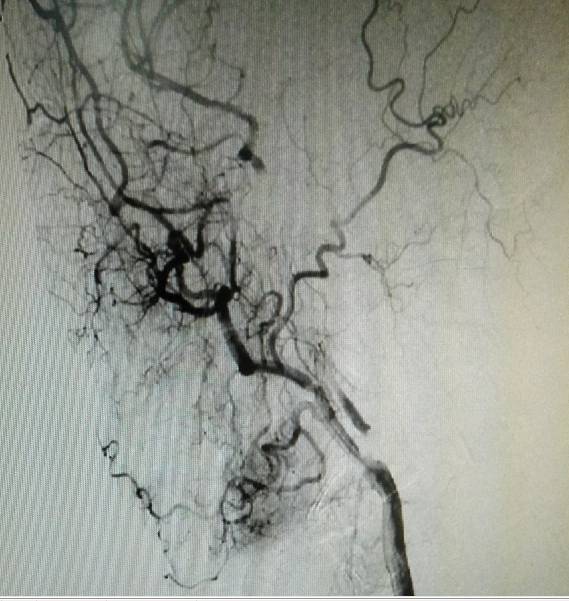

术前造影:右侧颈总动脉起始部显影,其余部位闭塞。颈外动脉向颈内动脉代偿供血。

手术过程:手术先切除颈总动脉动脉远端斑块,自远端颈内动脉处缝合至颈总动脉远端,夹闭颈总动脉远端,开放颈内动脉及颈外动脉,便于颈外动脉经颈内动脉向颅内代偿供血。再切除颈总动脉近端斑块,缝合后植入动脉鞘。视频如下。

经动脉鞘造影,可见颈总动脉通畅,但管腔狭窄,不规则。

然后球囊扩张,植入颈总动脉支架,造影示,右侧颈总动脉显影好。

此次分享两例颈动脉闭塞复合手术开通病例。第一例为颈内动脉长段闭塞,从颈内动脉起始段开始闭塞。患者术前存在眼动脉缺血事件及右侧半球灌注不足。颈内动脉剥脱后,颈内动脉可淡淡显影,为微导管通过创造条件。微导管通过后,顺利完成球囊扩张及支架植入,完全开通右侧颈内动脉。第二例为右侧颈总动脉闭塞患者,虽有颈外动脉代偿,但仍存在TIA及右侧大脑半球灌注不足。经颈动脉内膜剥脱后,造影可见颈总动脉显影,但管腔严重不规则,经球囊扩张及支架植入后,颈总动脉显影好。两例患者术后7天复查颈动脉CTA,均显示颈内动脉起始处较术后造影增粗。